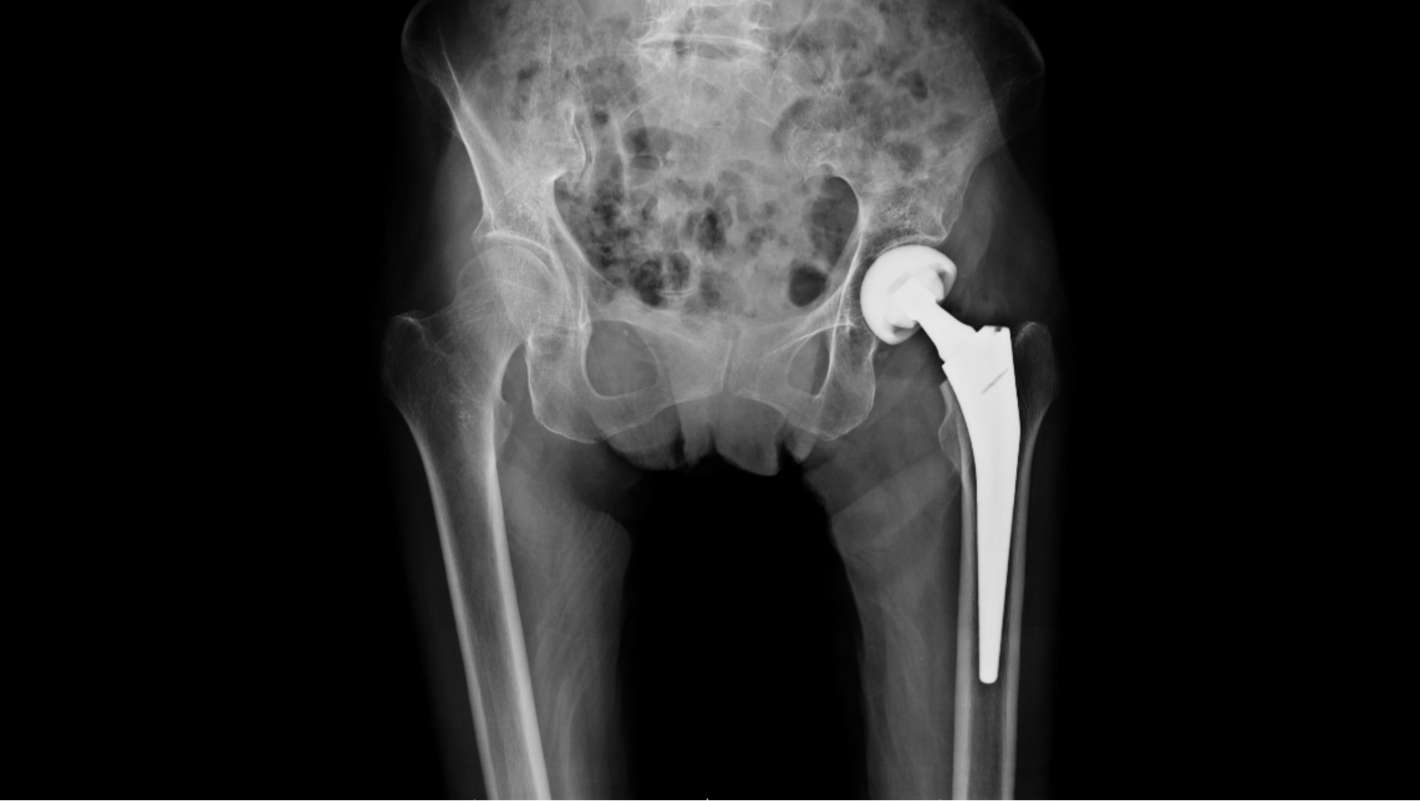

骨が治癒するまでの間、骨を所定の位置に保持するための、内部または外部のさまざまな手術があります。大腿骨骨折に対する最も一般的な手術は、髄内釘固定と呼ばれます。この手術では、上下のネジで骨の長さにロッドを挿入し、骨を所定の位置に保持します。